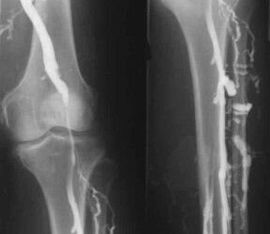

Cea mai comună metodă de diagnostic instrumental este utilizarea examinării cu ultrasunete a vaselor venoase ale picioarelor. Această tehnică vă permite să vizualizați sistemul vascular și să identificați gradul de progres al procesului patologic.

- Flebografie.